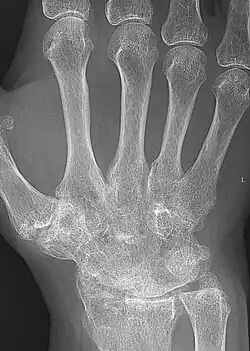

X-rays of the hands and feet are generally performed when many joints affected. In RA, there may be no changes in the early stages of the disease or the x-ray may show osteopenia near the joint, soft tissue swelling, and a smaller than normal joint space. As the disease advances, there may be bony erosions and subluxation. Other medical imaging techniques such as magnetic resonance imaging (MRI) and ultrasound are also used in RA.[23][56]

X-ray of the hand in rheumatoid arthritis. -

Closeup of bone erosions in rheumatoid arthritis.[58]